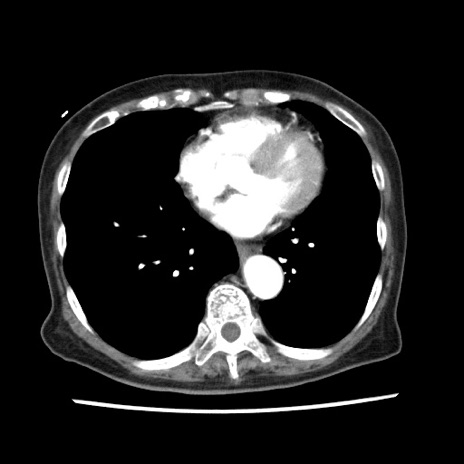

冠状断像

【症例】80歳代女性

【主訴】腹痛

【現病歴】8時間前から腹痛あり来院。

【既往歴】糖尿病、脂質異常症、子宮体癌にて子宮全摘術

【身体所見】意識清明・会話良好だが腹痛で苦悶様、全腹部にわたって反跳痛と圧痛あり

【データ】WBC 13600、CRP 0.14、LDH 224、CK 90